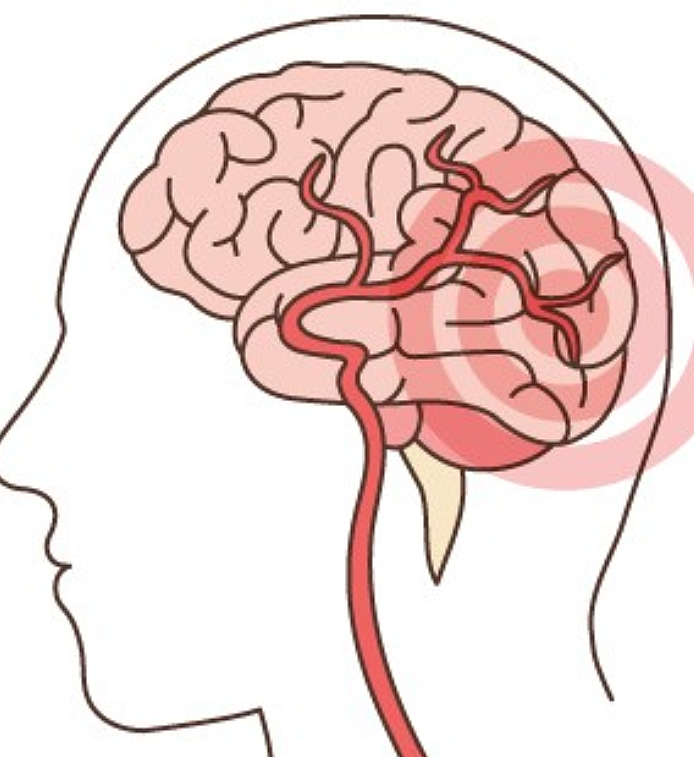

뇌졸중은 뇌 일부분에 혈액을 공급하는 혈관이 막히거나 터지면서 뇌가 손상돼 신경학적 이상이 나타나는 병입니다. 밤과 낮 그리고 실내외 온도 차가 계절에는 혈압 상승과 혈관 과부하로 심뇌혈관 질환 발병 우려가 매우 높습니다.

뇌에 혈액을 공급하는 혈관이 막히게 되면 뇌의 일부가 손상되는 ‘뇌경색 증상’, 뇌혈관이 터져 주변 뇌가 손상되는 ‘뇌출혈 증상’이 있습니다. 두 질병 모두 사망에 이르거나 뇌손상으로 인한 후유증이나 신체장애를 남길 수 있는 위험한 질환입니다.